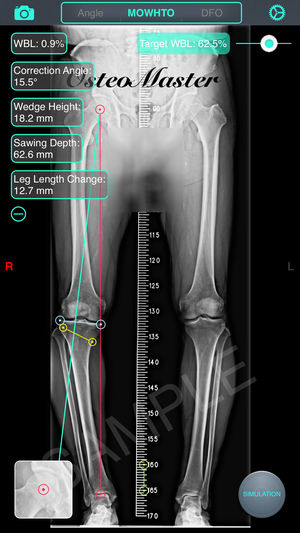

‎截骨神器 - 用于高胫骨截骨术(HTO)和股骨远端截骨术(DFO)的手术前术前规划工具。 特征: 1. 测量骨骼的解剖或力学軸角度,只需通过相机或照片库输入图像。 2. 计算术前负重线(WBL)和规划目标WBL。 3. 自动计算截骨矫正角度、楔块高度、切锯深度与脚长变化。 4. 设定期望WBL,矫正角度,缺口高度,MPTA或LDFA 5. 提供開放(open)或閉合(close)、内侧(medial)或外侧(lateral)截骨。 6. 模拟截骨调整后结果。 教学視頻:https://v.qq.com/x/page/h0527kc4vj1.html 簡体用户指南:http://pan.ba…